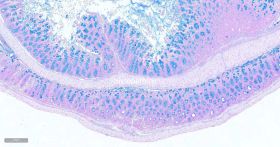

瑞士肠卷阿利新蓝染色:

阿利新蓝.jpg

染色结果:

酸性硫酸化粘液物质:蓝色

透明质酸:蓝色

唾液黏蛋白:蓝色

细胞核:红色